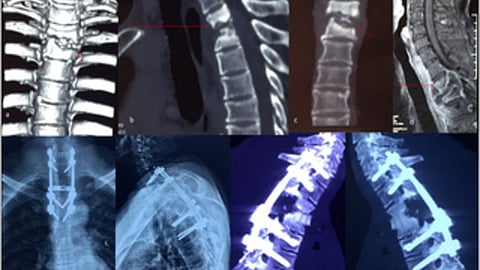

Doctors at Fortis Hospital Shalimar Bagh diagnosed her condition as spinal tuberculosis. An MRI disclosed spinal tuberculosis with severe spinal cord compression. Urgent surgery was required to relieve the pressure and stabilize her spine, said the doctors. Due to her pregnancy, the surgical procedure was complex. The doctors had to make her lie down in such a way that no pressure was exerted on the abdomen or fetus.

Unable to use traditional spinal fixation methods due to pregnancy-related X-ray restrictions, the doctors could not put screws in the unstable spine. But, as it was mandatory to insert screws (intervertebral titanium cage), the surgeons opted for a temporary wire fixation.

Post-delivery, after 15 days, unfortunately, an MRI revealed severe spinal cord swelling and an unstable collapsed spine with spinal cord compression.

To overcome this, another surgery was conducted through the side of her lung to remove tuberculosis tissue and stabilize the spine, involving the placement of a cage and screws to bridge the vertebral gap.

Three months after her surgery, the woman showed no leg movement, prompting a repeat MRI that showed ongoing spinal cord swelling.